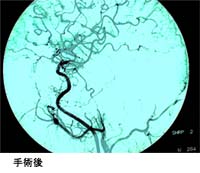

無理であれば動脈瘤頚部のクリッピングに拘らず、以下に示しました血管吻合術を利用して正常血管の血流を維持したうえで、動脈瘤の前後で血流を遮断し破裂しないようにします。巨大脳動脈瘤の治療は、一筋縄ではいかないことが多いのですが、私たちは様々な方法を用いて治療しています。 動脈瘤に入る血管を結紮して閉塞し、脳の血流はバイパスの血管にて流れています。